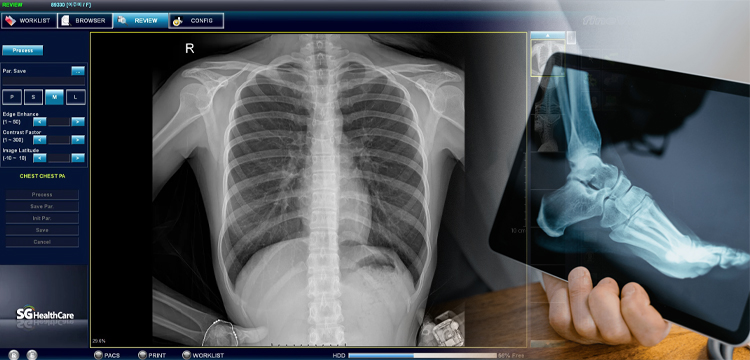

Contamos con equipos de rayos x digitalizados para la realización de cualquier estudio Radiologico como son:

• Radiografía de Tórax